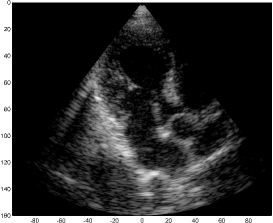

We examine the result of applying our scheme of Fig. 2 to raw RF data, acquired and stored for cardiac images of a healthy consenting volunteer. The acquisition was performed using a breadboard ultrasonic scanner of 64 acquisition channels. The transducer employed was a 64-element phased array probe, with central frequency, operating in second harmonic imaging mode: 3 half cycle pulses are transmitted at , resulting in a signal characterized by a rather narrow bandpass bandwidth, centered at . The corresponding second harmonic signal, centered at , is then acquired. The signal detected in each acquisition channel is amplified and digitized at a sampling-rate of . Data from all acquisition channels were acquired along 120 beams, forming a sector, where imaging to a depth of , we have . The results are illustrated in Fig. 3.

The first image (a) was generated using the standard technique, applying beamforming to data first sampled at the Nyquist rate, and then down-sampled, exploiting its limited essential bandwidth. For a single image line, sampling at , we acquire real-valued samples from each element, which are then down-sampled, to real-valued samples, used for beamforming. The resulting image is used as reference, which we aim at reproducing with our Xampling scheme. We begin by applying our scheme without approximation, simulating the modulation with the analog kernels defined in (11). Assuming reflectors, and using two-fold oversampling, comprises indices. Since each sample is complex, we get an eight-fold reduction in sample-rate. The resulting image (b) well depicts strong perturbations observed in (a). Isolated reflectors at the proximity of the array () remain well in focus. Applying our approximated scheme, for every , and , we choose and of (13) such that . At the current stage, this choice, and consequently the choice of and , are performed off-line, based on the imaging setup. This results in an average number of complex samples per receiving element, required for constructing each image line (with at most samples required for some combinations of and element indices). We arrive at a seven-fold reduction in sample rate, and the resulting image (c) appears very similar to (b).